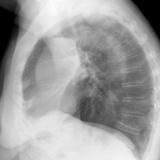

LUL Collapse Case 1 Lateral

Date: 02/19/2004

Views: 3319